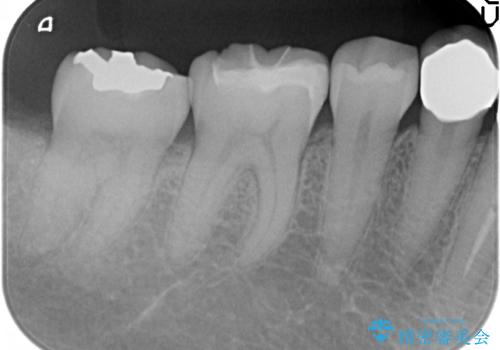

- 右下6番目の歯の舌側に虫歯があるので治療して欲しいといらっしゃった方の症例です。

古い銀歯及び虫歯を除去後、セラミックインレーにて修復を行いました。

虫歯治療は虫歯の進行度によって処置が変わってきます。

虫歯が小さければ、インレー・クラウン等による修復・補綴処置を行うだけで済みます。

しかし虫歯が大きくなると神経処置や抜歯等をしなければならない場合もあります。